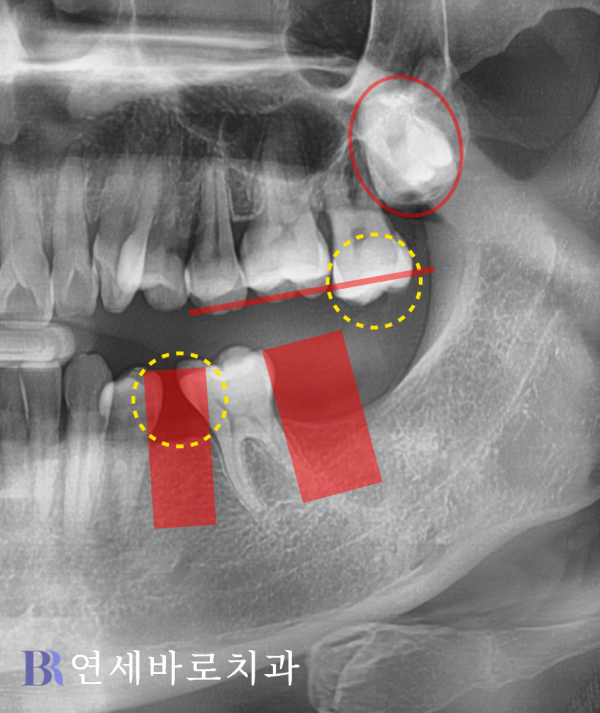

여러분께서 좀 더 자세하게

확인해보실 수 있으시도록

사진을 더 확대해보았습니다.

빨간색 사각형으로 매식체가

들어갈 위치를 표시했습니다.

탈락한 곳이 오래 방치되어

어금니가 앞으로 기울었네요.

뿐만 아니라 상악에서는

큰 어금니가 사랑니에 밀려

밑으로 내려온 상태였습니다.

임플란트를 완성시킴으로써

정상적인 교합을 이루려면

앞으로 기운 어금니 일부와

상악의 대합치를 부분적으로

삭제할 수 밖에 없었습니다.